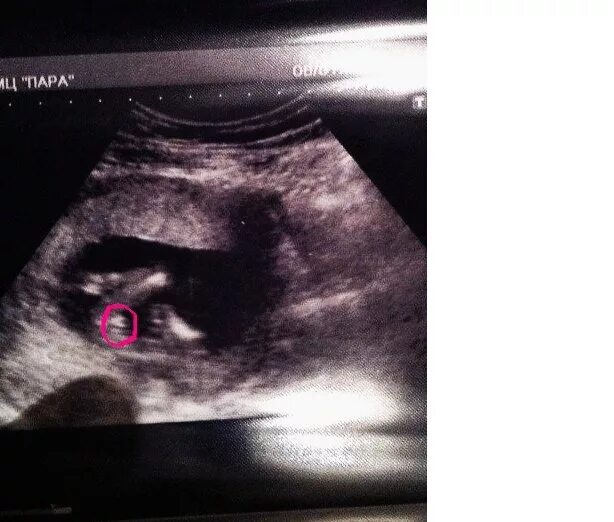

15 неделя можно узнать пол ребенка